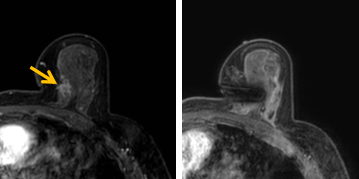

患者李女士磁共振檢查發(fā)現(xiàn)右乳內(nèi)側(cè)高度可疑病變,病變小摸不到,超聲和X線攝影(鉬靶)都看不到,怎么辦?要想明確病變性質(zhì),必須進(jìn)行磁共振引導(dǎo)下精準(zhǔn)足量的活檢,但是這種技術(shù)操作難度大、軟硬件要求高。

經(jīng)過(guò)仔細(xì)查體并分析所有影像資料,陳寶瑩發(fā)現(xiàn),病變靠近胸大肌,容易造成術(shù)中損傷?;颊呷榉枯^小,病變?cè)趦?nèi)側(cè),導(dǎo)致乳房不易固定,進(jìn)針難度大,與患者充分溝通后,陳寶瑩帶領(lǐng)團(tuán)隊(duì),制定了細(xì)致的操作方案,術(shù)中,醫(yī)護(hù)團(tuán)隊(duì)反復(fù)調(diào)整體位和固定架的角度及方向,利用隔離技術(shù)保護(hù)好周圍組織。受乳房形態(tài)和病變位置的限制,醫(yī)生只能蹲著、跪著進(jìn)行操作,經(jīng)過(guò)30多分鐘終于順利完成,精準(zhǔn)獲取了足量的組織,而且一針到位,創(chuàng)傷小、出血少,患者沒(méi)有任何不適,做完即回家休息。幾天后,病理證實(shí)是一種特殊類型的早期乳腺癌,為后續(xù)進(jìn)一步治療方案的制訂提供了準(zhǔn)確依據(jù)。